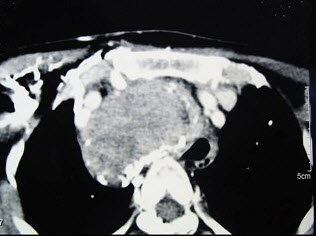

- 多项选择题女性,48岁,颈部包块3年,近来胸闷、憋气、胸痛,CT扫描如图,请选择正确的描述和答案()。

A、考虑为胸骨后甲状腺肿

B、考虑为血管瘤

C、考虑为双侧甲状腺肿大

D、胸骨后甲状腺肿是指甲状腺50%位于胸骨后

E、胸骨后甲状腺肿是指甲状腺60%位于胸骨后

- A,D